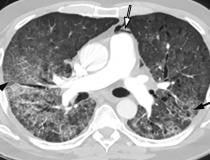

This photo gallery shows the variety of radiological presentations of COVID-19 (SARS-CoV-2) in medical imaging, including computed tomography (CT), radiograph X-rays, ultrasound, echocardiograms and magnetic resonance imaging (MRI). The radiology images show examples of typical COVID pneumonia in the lungs and the numerous complications the virus causes in the body in multiple organs, including the brain, kidneys, heart, abdomen and vascular system.